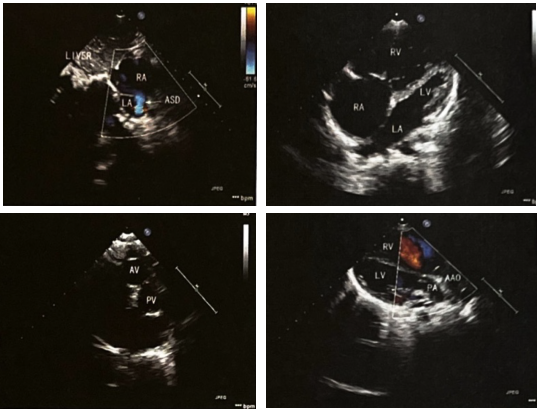

◆急诊床旁超声心动图示:先天性复杂性心脏病,内脏、心房正位,左位心,心室右袢,房室连接一致,完全性大动脉转位(S,D,A),室间隔完整,房间隔缺损(中央型,双向分流),动脉导管未闭(图3)。

(9).png)

◆初步诊断:先天性心脏病,完全型大动脉转位(TGA/IVS),房间隔缺损(ASD),动脉导管未闭(PDA)。